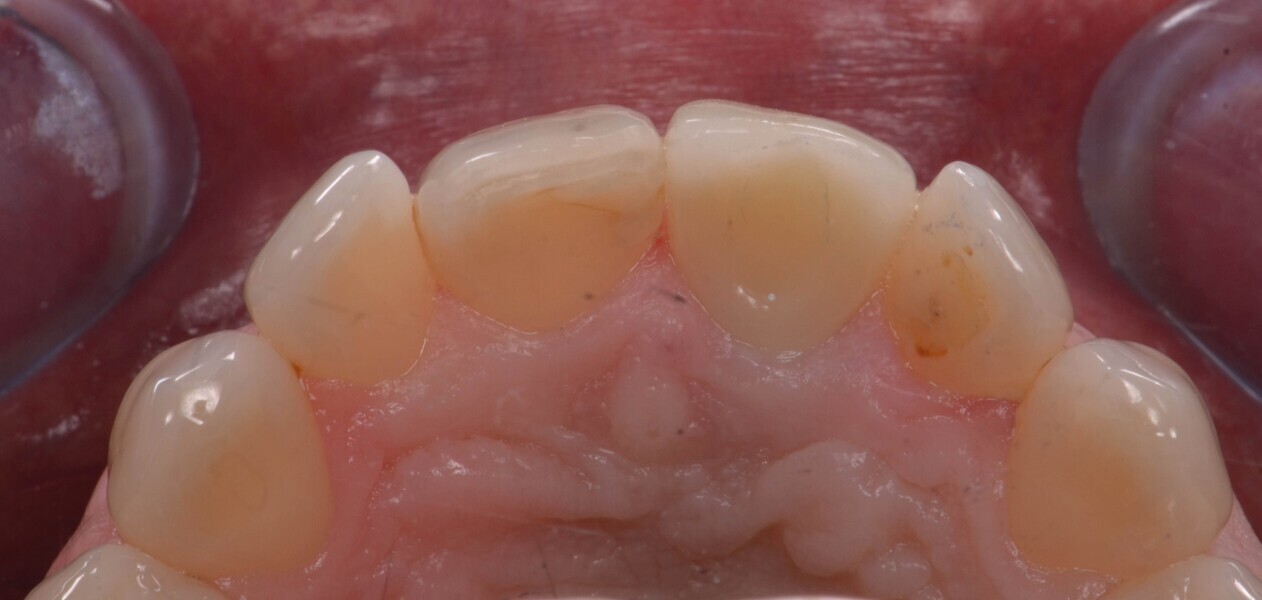

Fig. 20a : Couronne définitive implanto-portée, vue extraorale ;

Fig. 20b : Couronne définitive implanto-portée, vue occlusale.